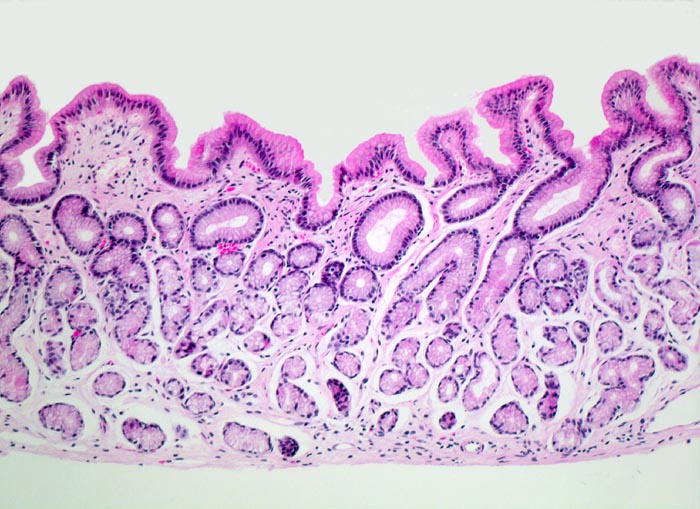

PathoPic – image database / PathoPic ID 4392 - normales Magenantrum

normales Magenantrum

Magenantrum

Die Foveolae im Magenantrum sind tiefer als im Corpus (bis zu 50% der gesamten Mukosabreite). Die pylorischen Schleimdrüsen sind ausgekleidet durch hochprismatische Zellen mit hellem Zytoplasma. Die Lamina propria ist weitgehend frei von Entzündungszellen.

Histologie

100